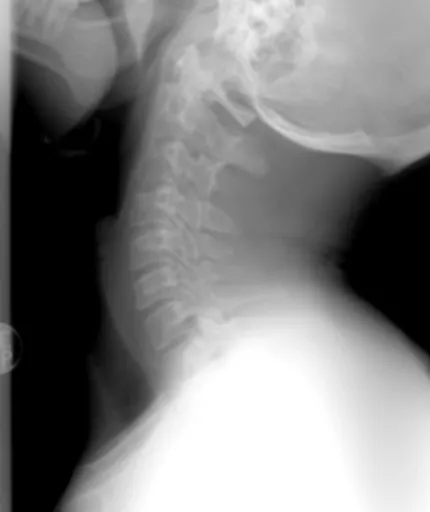

류마티스 관절염 초기 증상 을 의심하고 병원을 찾으면, 의사 선생님께서는 여러 가지 방법으로 진단을 내리게 돼요. 먼저, 환자의 증상과 병력을 꼼꼼하게 듣고, 신체검진을 통해 관절의 붓기, 열감, 운동 범위 등을 확인하게 됩니다. 그리고 혈액검사를 통해 류마티스 인자(RF)나 항CCP 항체 같은 특정 항체의 수치를 확인하고, 염증 수치(ESR, CRP)를 통해 염증의 정도를 파악하게 돼요. 또한, X-ray, 초음파, MRI 등의 영상 검사를 통해 관절의 손상 정도나 염증 부위를 확인하면서 정확한 진단을 내리게 된답니다. 이런 종합적인 검사를 통해 류마티스 관절염 을 조기에 진단하고 적절한 치료 계획을 세우는 것이 중요해요.